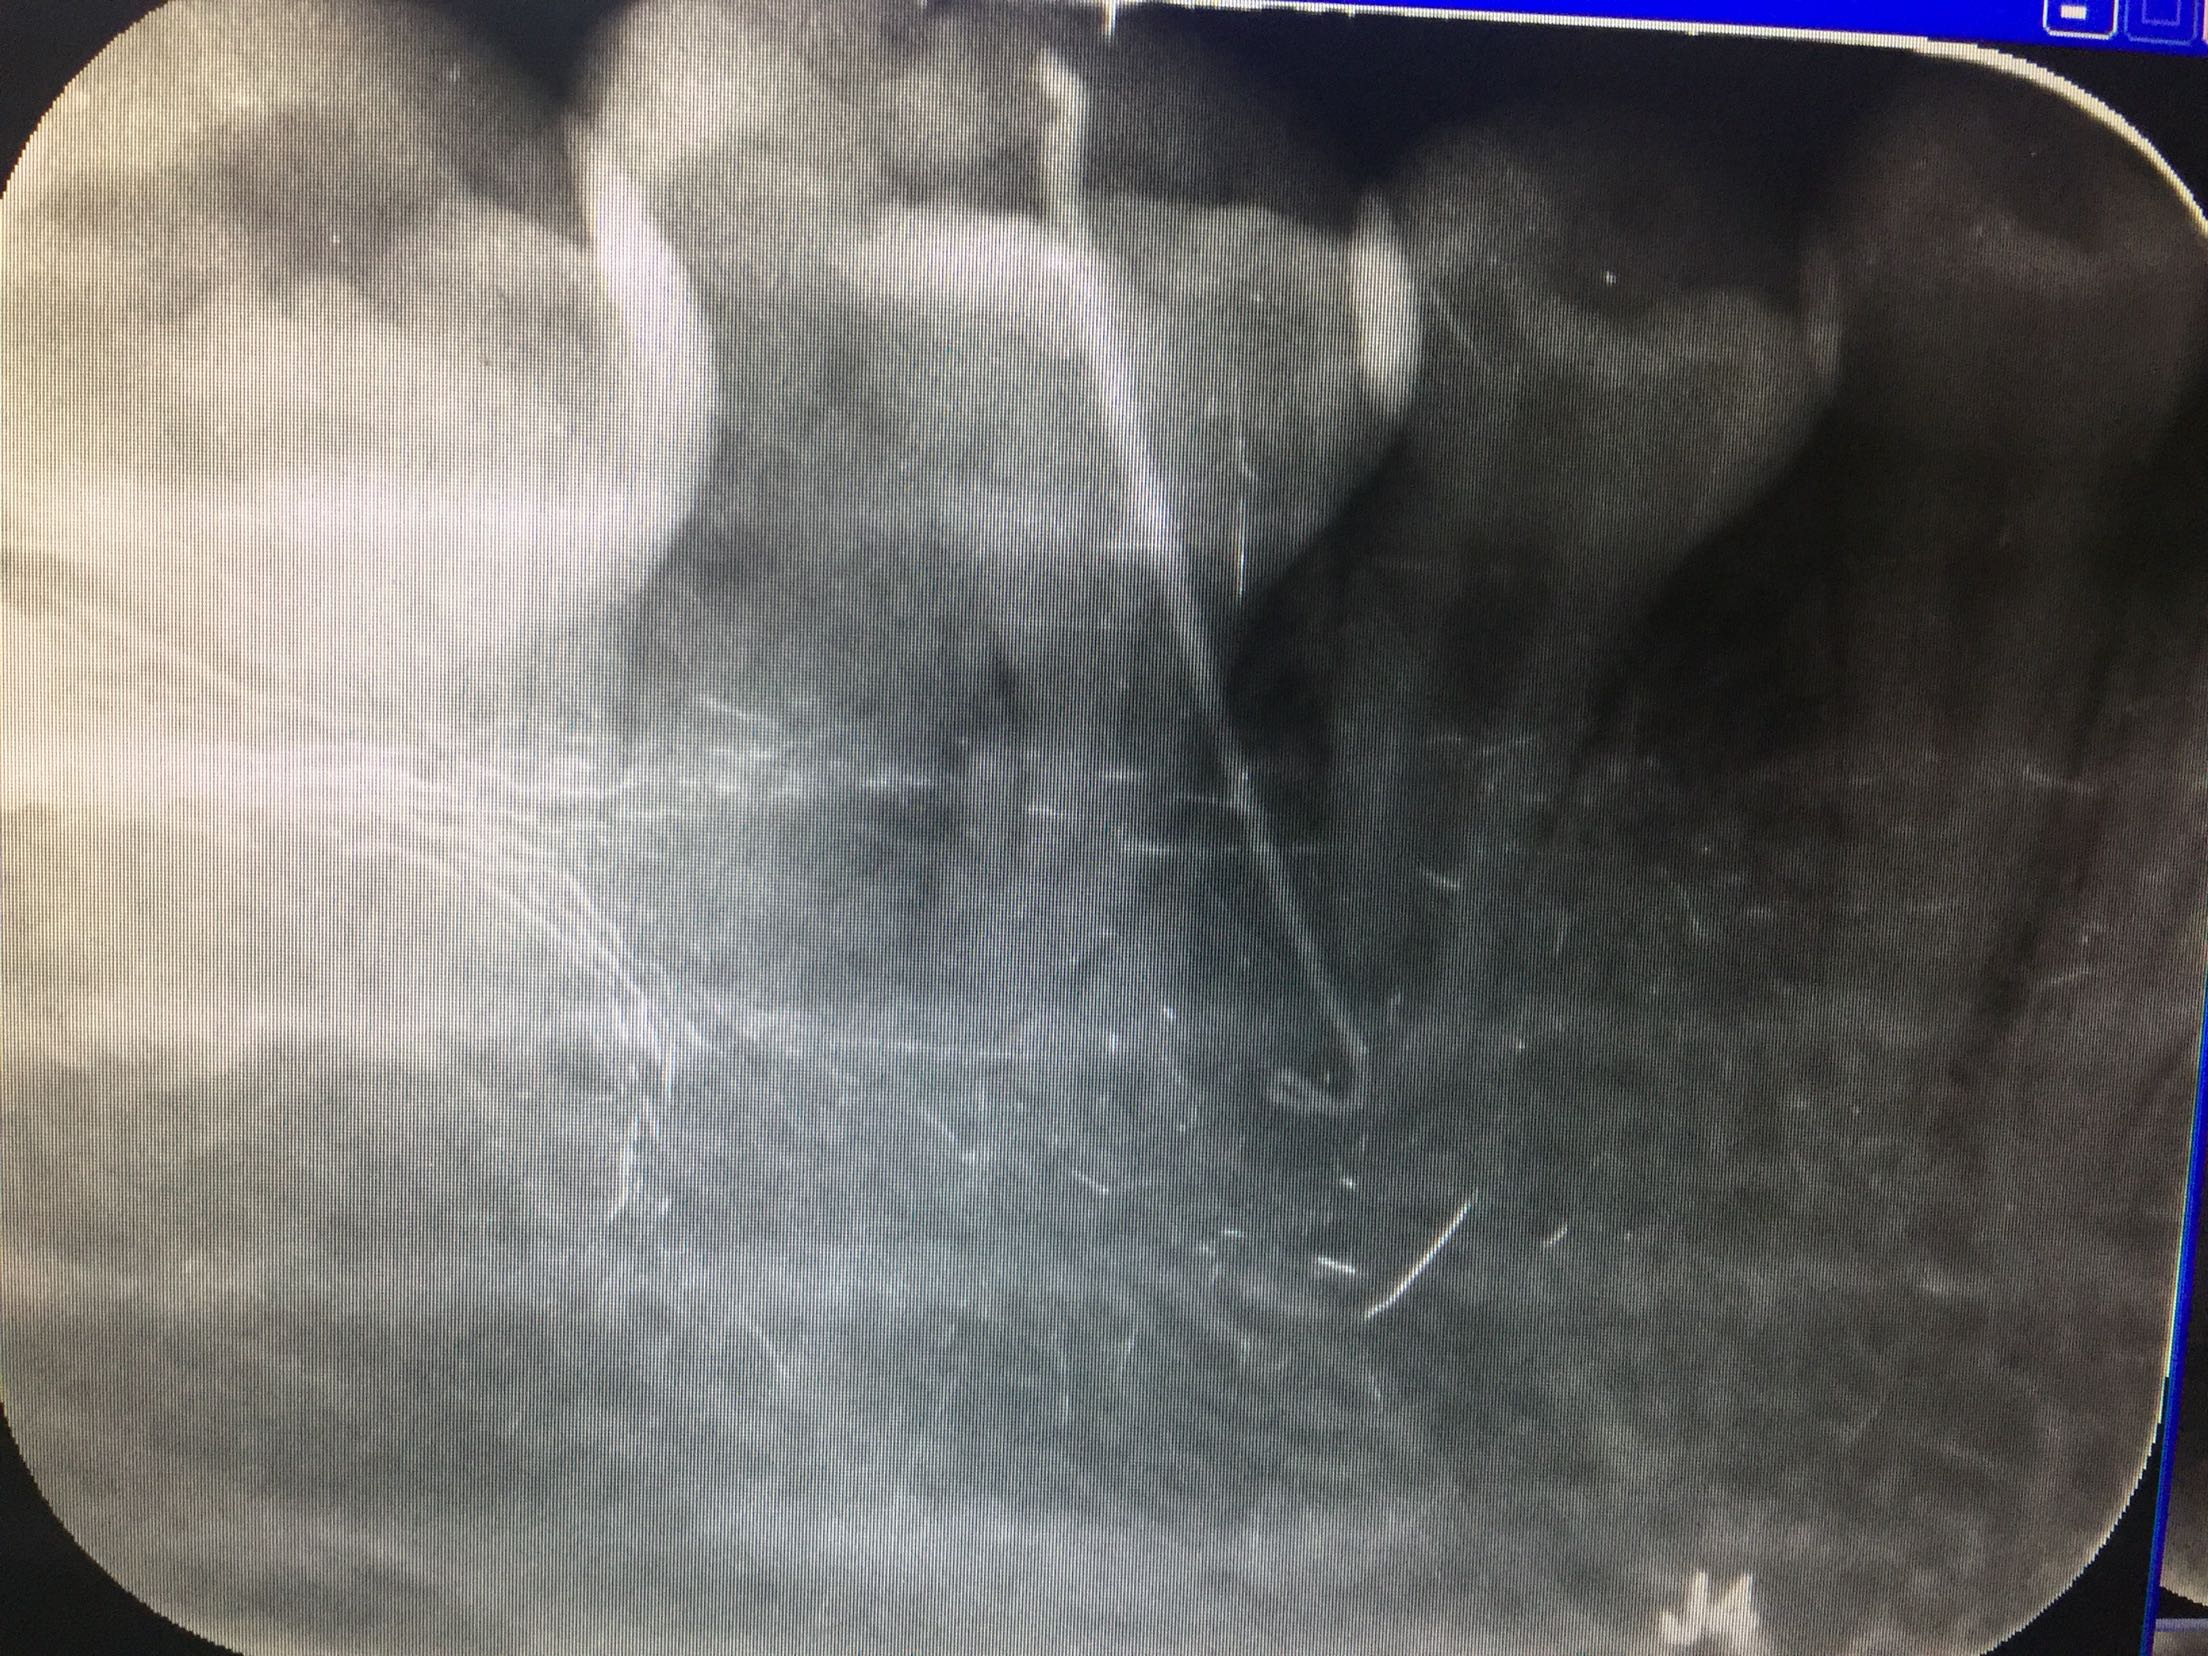

检查:45畸形舌侧尖磨耗,未见明显龋及隐裂,叩诊(+),松动不明显,颊侧牙龈瘘管,挤压有少量脓液,冷诊(-)。 全口牙列拥挤,排列不齐。 辅查:45根尖呈喇叭口状,根尖区低密度影像,于瘘管处插牙胶尖示踪瘘管来源于45根尖处。